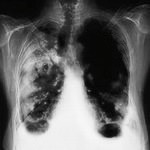

К сожалению, в большинстве случаев это заболевание протекает совершенно бессимптомно. Кашель, боли в грудине, мокрота появляются лишь тогда, когда случай уже запущен, то есть в 3-й, 4-й стадии. А в первой стадии этот вид рака выявить, как правило, очень трудно. Это возможно только при периферической опухоли.

При выявлении заболевания в первой стадии вероятность излечения составляет 80%, во второй — 40%, в третьей — 20%, в четвертой стадии — 0%.

Да. Я считаю это достижением советского здравоохранения. В связи с этим и выявляемость рака легкого в бывшем Советском Союзе была одной из самых высоких в мире. Периферическую опухоль легкого при флюорографии можно обнаружить даже на первой стадии (опухоль до 1 см)! И в основном те больные, которые поступают к нам в клинику на ранних стадиях, узнали о своем диагнозе именно после планового прохождения флюорографии. Хотя рак, располагающийся в центре легкого либо в бронхах, к сожалению, выявить с ее помощью гораздо сложнее.

В Минске в среднем ежегодно заболевает раком легкого около 500 человек. Основную массу больных составляют мужчины после 50-ти лет. Радикальное лечение, то есть операция, проводится в среднем 120 больным, или 25% пациентов. Если сравнить с мировыми показателями, то в мире оперируют в среднем 15% пациентов. А в СCCР в связи с ежегодным прохождением флюорографии и отсюда более ранним выявлением заболевания, радикальному лечению подвергались 20% заболевших. И именно операция значительно повышает шансы на выживание.